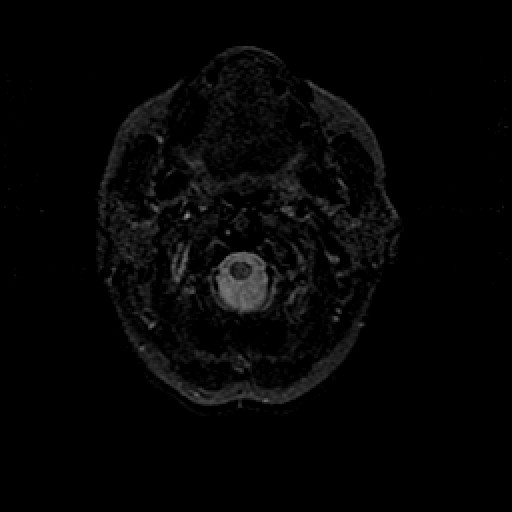

T2-weighted structural MR: Slice 3

Slice 3